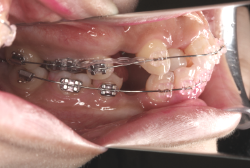

今回は「歯並びの凸凹を治したい」という主訴で来院したケースです。診断の結果、「成長発育期の叢生」と判明しました。叢生とは歯並びの凸凹のことですが、この方の場合は上顎が少々重症で、上の犬歯が外側へ飛び出し、いわゆる「八重歯」という状態でした。凸凹の解消のためには永久歯を抜歯して隙間を作って残った歯をきれいに配列する方法(抜歯法)と、歯列を拡大して配列する方法(非抜歯法)の2種類があります。歯列の拡大にはさらに2つの方法が有り、横方向へ拡大する場合と、臼歯を後方に移動させて拡大する方法があります。今回の症例のようなケースでは、横方向へ拡大してもあまり効果的ではなく、後方への移動が最適です。上の臼歯を後方へ移動させるために、今回はヘッドギヤという取り外し式の装置を、夜寝る時に半年ほど使用していただきました。

注意点としてここでお伝えしたいのは、矯正専門医ではない歯科医院で、いわゆる「床矯正」という方法を行うと、たいてい横方向の拡大になってしまいます。無駄に横方向の拡大をするとかえって症状を悪化させたり、何の効果もないことになってしまいます。一見簡単そうな矯正に見えたとしても、しかるべき矯正専門医に診断してもらうことをおすすめします。

この方の場合、治療期間はヘッドギアを6ヶ月、マルチブラケット法を7ヶ月でした。治療後は凸凹が改善しただけでなく唇の審美性が大幅に改善しました。もちろん噛み合わせ的にも正しい状態が確立しています。